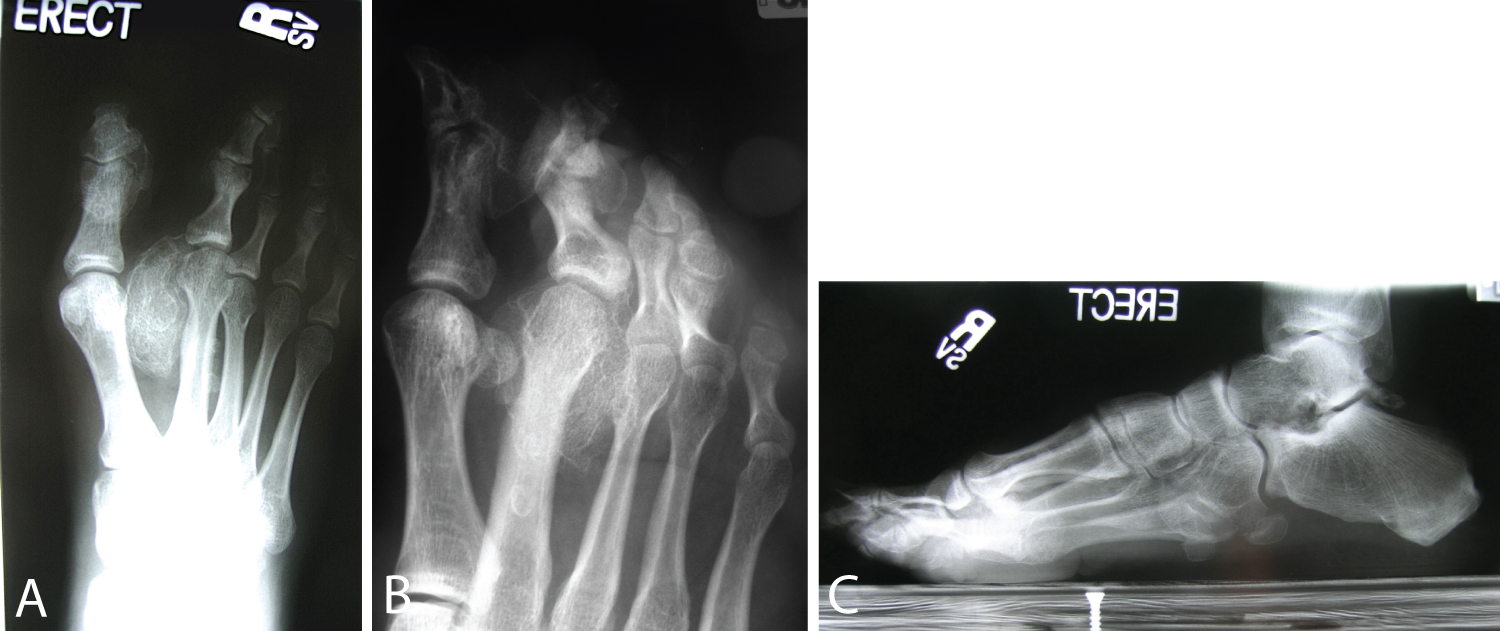

Our patient is a 20-year-old female, NCAA Division II collegiate soccer player, who presented to the office with progressive deformity and pain of the right foot and second toe that has been worsening over one year. At age 5, she was diagnosed with PS with the right foot overgrowth as the presenting symptom. Her symptoms progressed to the point where prolonged standing would cause her pain and thus rendered her unable to continue her athletic endeavors, limited her shoe wear, and began to affect her ability to perform every day activities. Due to the deformities and multiple bony masses, she was forced to wear a size 11 shoe on the right foot, as compared to size 7 on the uninvolved, left foot. On exam, she has developed thick callosities in the plantar webspace in between the first and second metatarsal and plantar-medial aspect of the great toe. Skin changes typical of PS, cerebriform lesions, were present on the plantar-medial aspect of her right foot (Figure 1A and Figure 1B). Neurologic exam was normal. Vascular exam revealed 2+ pedal pulses and markedly enlarged veins were observed in both extremities. Limited motion of the metatarsophalangeal and interphalangeal joints of all digits was noted for the right foot. The second toe had significant overgrowth and an associated bony prominence between the first and second metatarsals measuring 3.5 × 3 cm. Upon weight bearing, this would push her great toe cephalad causing the toe to not sit properly on the ground, creating a dynamic cock-up toe deformity. The hindfoot was in varus with weight bearing, along with her great toe not making appropriate ground contact. A cavovarus foot posture resulted with development of a painful lateral overload syndrome (Figure 1C and Figure 1D). Weight-bearing X-rays demonstrated a large amount of well-corticated heterotopic bone formation in the first webspace encircling the distal neck and head region of the right second metatarsal. Other bony masses were identified at the plantar-medial aspect of the great toe, Plantar Proximal Interphalangeal (PIP) of the third toe and, to a lesser extent, lateral border of the foot (Figure 2A, Figure 2B and Figure 2C).

Figure 2: Weightbearing X-ray films of the right foot revealed a large amount of well-corticated heterotopic ossification encompassing and encircling the second metatarsal, along with smaller bony masses over the plantar-medial aspect of the great toe, plantar PIP area of the third toe and lateral border of foot: (A) AP view, (B) Oblique view and (C) Lateral view. View Figure 2